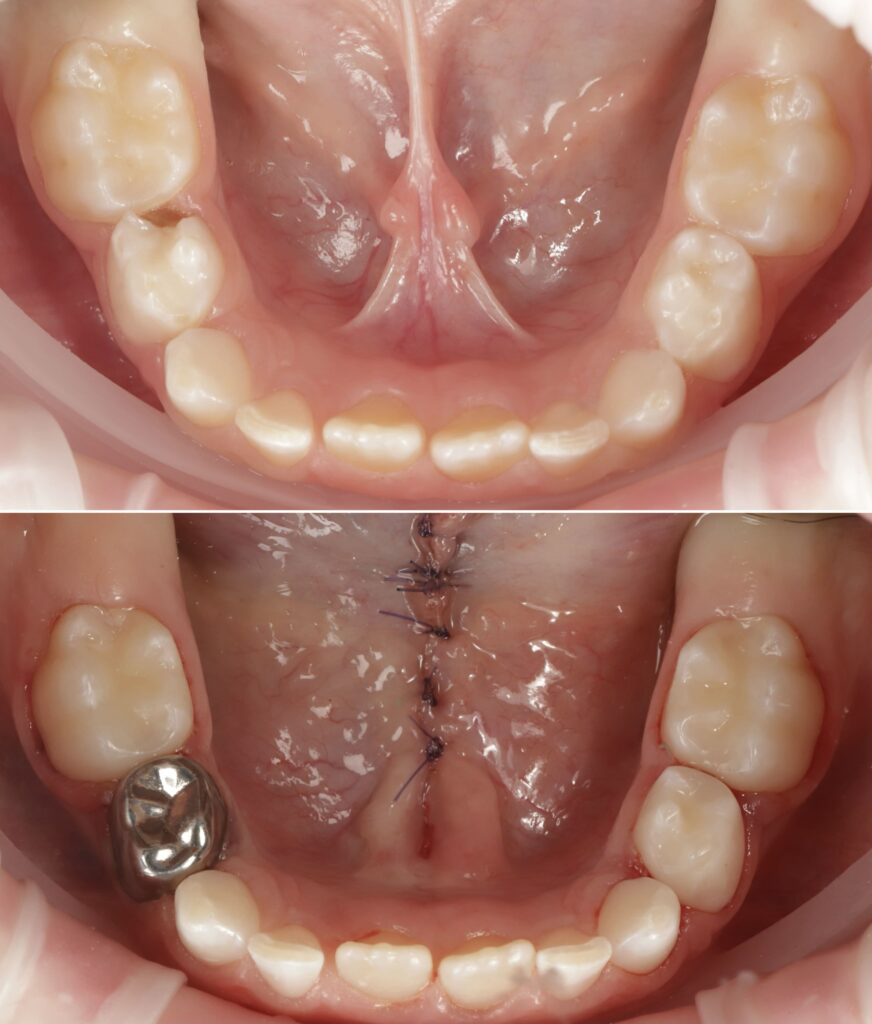

- Лікар після дії анестезії підрізає вуздечку скальпелем, потім накладає косметичний шов. Шви після операції розсмоктуються самостійно через 7-10 днів.